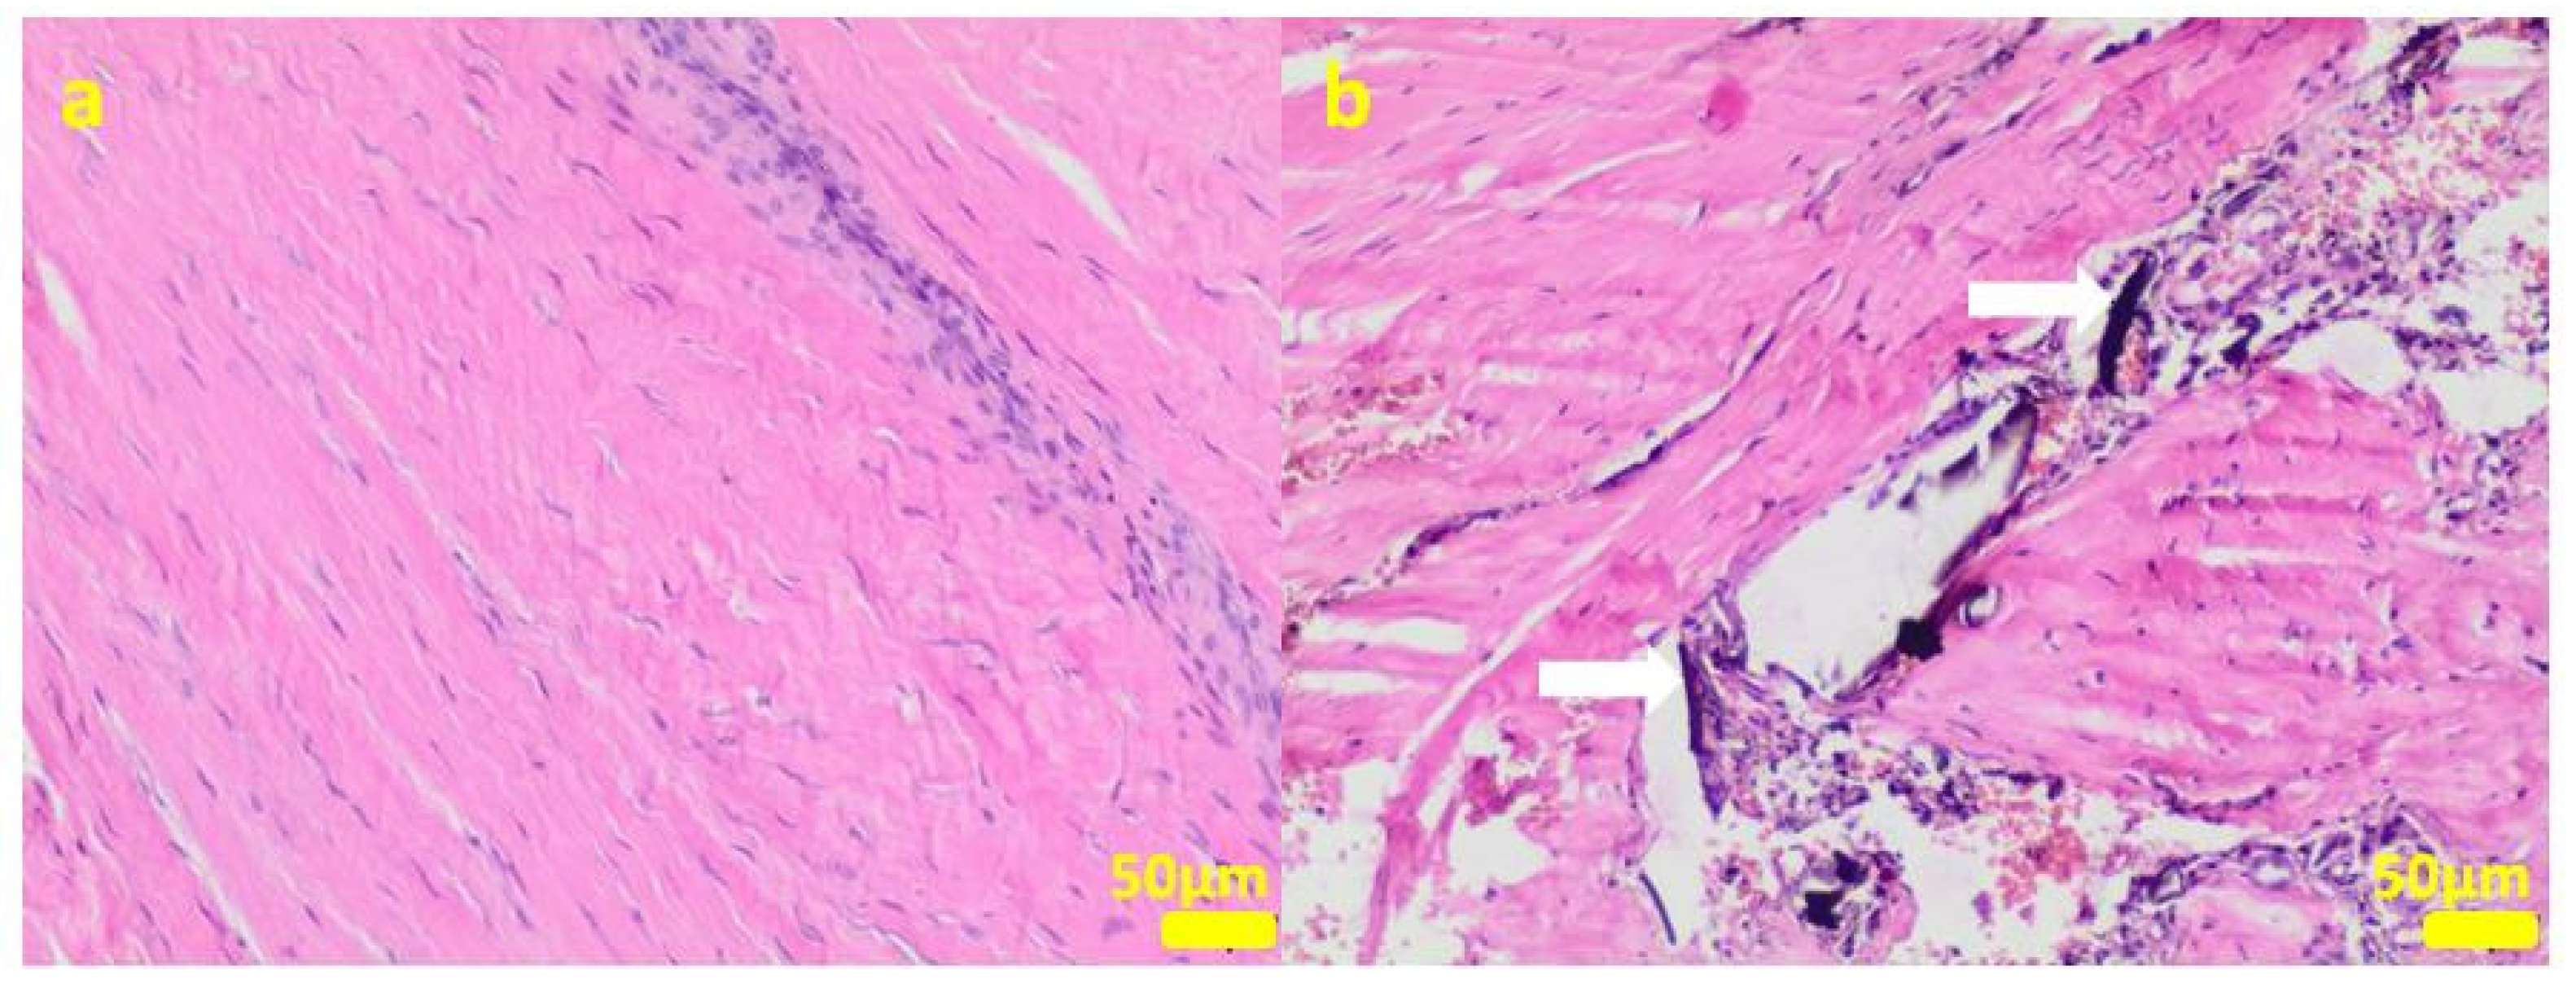

During the removal procedure, the implant proved to be very well-adhered to the tissue. The microscopic examinations of the collected samples (all the tissues collected after 3 months of implantations from the implant/bone contact area; each sample from the different patient) did not reveal microorganisms. Moreover, there was no inflammatory response suggesting a bacterial infection (Figure 6, Figure 7, Figure 8, Figure 9 and Figure 10). Although inflammatory infiltrates were found, they were more typical for a foreign body reaction (granulomatous inflammation in sample 1) or a chronic antigenic stimulation (plasmocytic infiltrate in sample 6).

Figure 8.

Sample 3:the compact fibrous connective tissue (a). Sample 4:the compact fibrous connective tissue with fine fibrillar material and black pigment (white arrow; (b)). Hematoxylin-eosin staining, magnification 100×.

The microscopic lesions observed in the examined samples suggested the correct tissue reparation process, starting from the granulation tissue up to the mature compact fibrous tissue that is typical for postsurgical scars. The implant, i.e., the TPLO plate and screws covered in the hybrid layer containing silver nanoparticles, seemed to facilitate the healing process; therefore, some features of granulomatous inflammation and plasmocytic perivascular infiltrates were present in the examined samples. Generally, both such microscopic findings and soft tissue calcification processes are observed in a natural healing process.